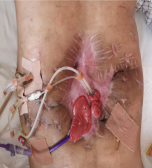

本次交流的重点病例是一名车祸伤术后多发肠瘘、腹腔出血、腹腔开放的34岁青年男性,车祸伤急诊手术后出现并发症,在25天内因为反复肠瘘、腹腔出血又被迫进行了四次急诊腹部手术,最终导致了严重的多发肠瘘及腹腔开放,于2018年1月25日转来我院重症监护病房。入院后经过水电解质紊乱纠正、脏器功能维持、腹腔感染控制,病情得到逐步控制后转回胃肠外科病房进行后续的冲洗引流、营养支持等综合治疗,使得腹壁创面逐步缩小,患者体力明显改善。

经过了充分的术前评估和讨论后于2018年8月21日进行确定性手术治疗,手术过程是惊心动魄的一天,手术难度非常大,包括复杂肠粘连松解、多发肠瘘切除、消化道重建与腹壁重建,手术历时10个小时。手术的难点是十二指肠瘘和腹壁缺损的处理。因为十二指肠瘘口范围较大,而且是炎性瘢痕组织,不能单纯缝合,十二指肠切除极有可能造成危及病人生命的大出血,因此李元新主任游离了一部分小肠与十二指肠瘘口吻合,并预想到术后会发生吻合口瘘,因此在吻合口周围放置好引流管,术后虽然确实发生了十二指肠瘘,但经过保守治疗最终用生物蛋白胶进行封堵成功。

另一手术难点是腹壁重建,因为本病人经历多次手术,两侧腹壁及胸壁瘢痕组织严重,加之多次放置多跟引流管,导致腹壁两侧无法游离及转移皮瓣,导致皮肤无法关闭,李元新主任手术团队再次应用大网膜替代皮肤组织的策略成功关闭患者腹腔,避免了诸多相关并发症的再次发生。